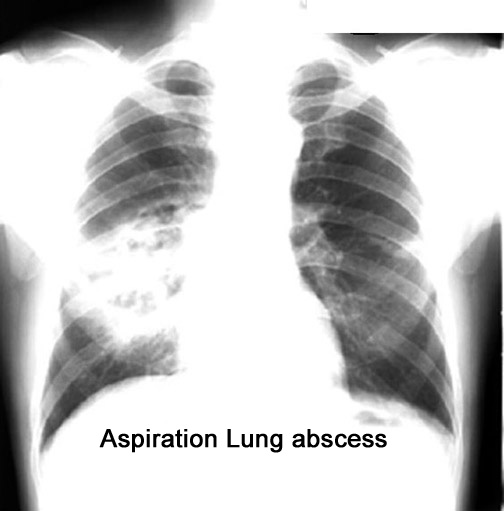

Labeled Image What are the common segments for aspiration lung abscess?

What are the types of aspiration?